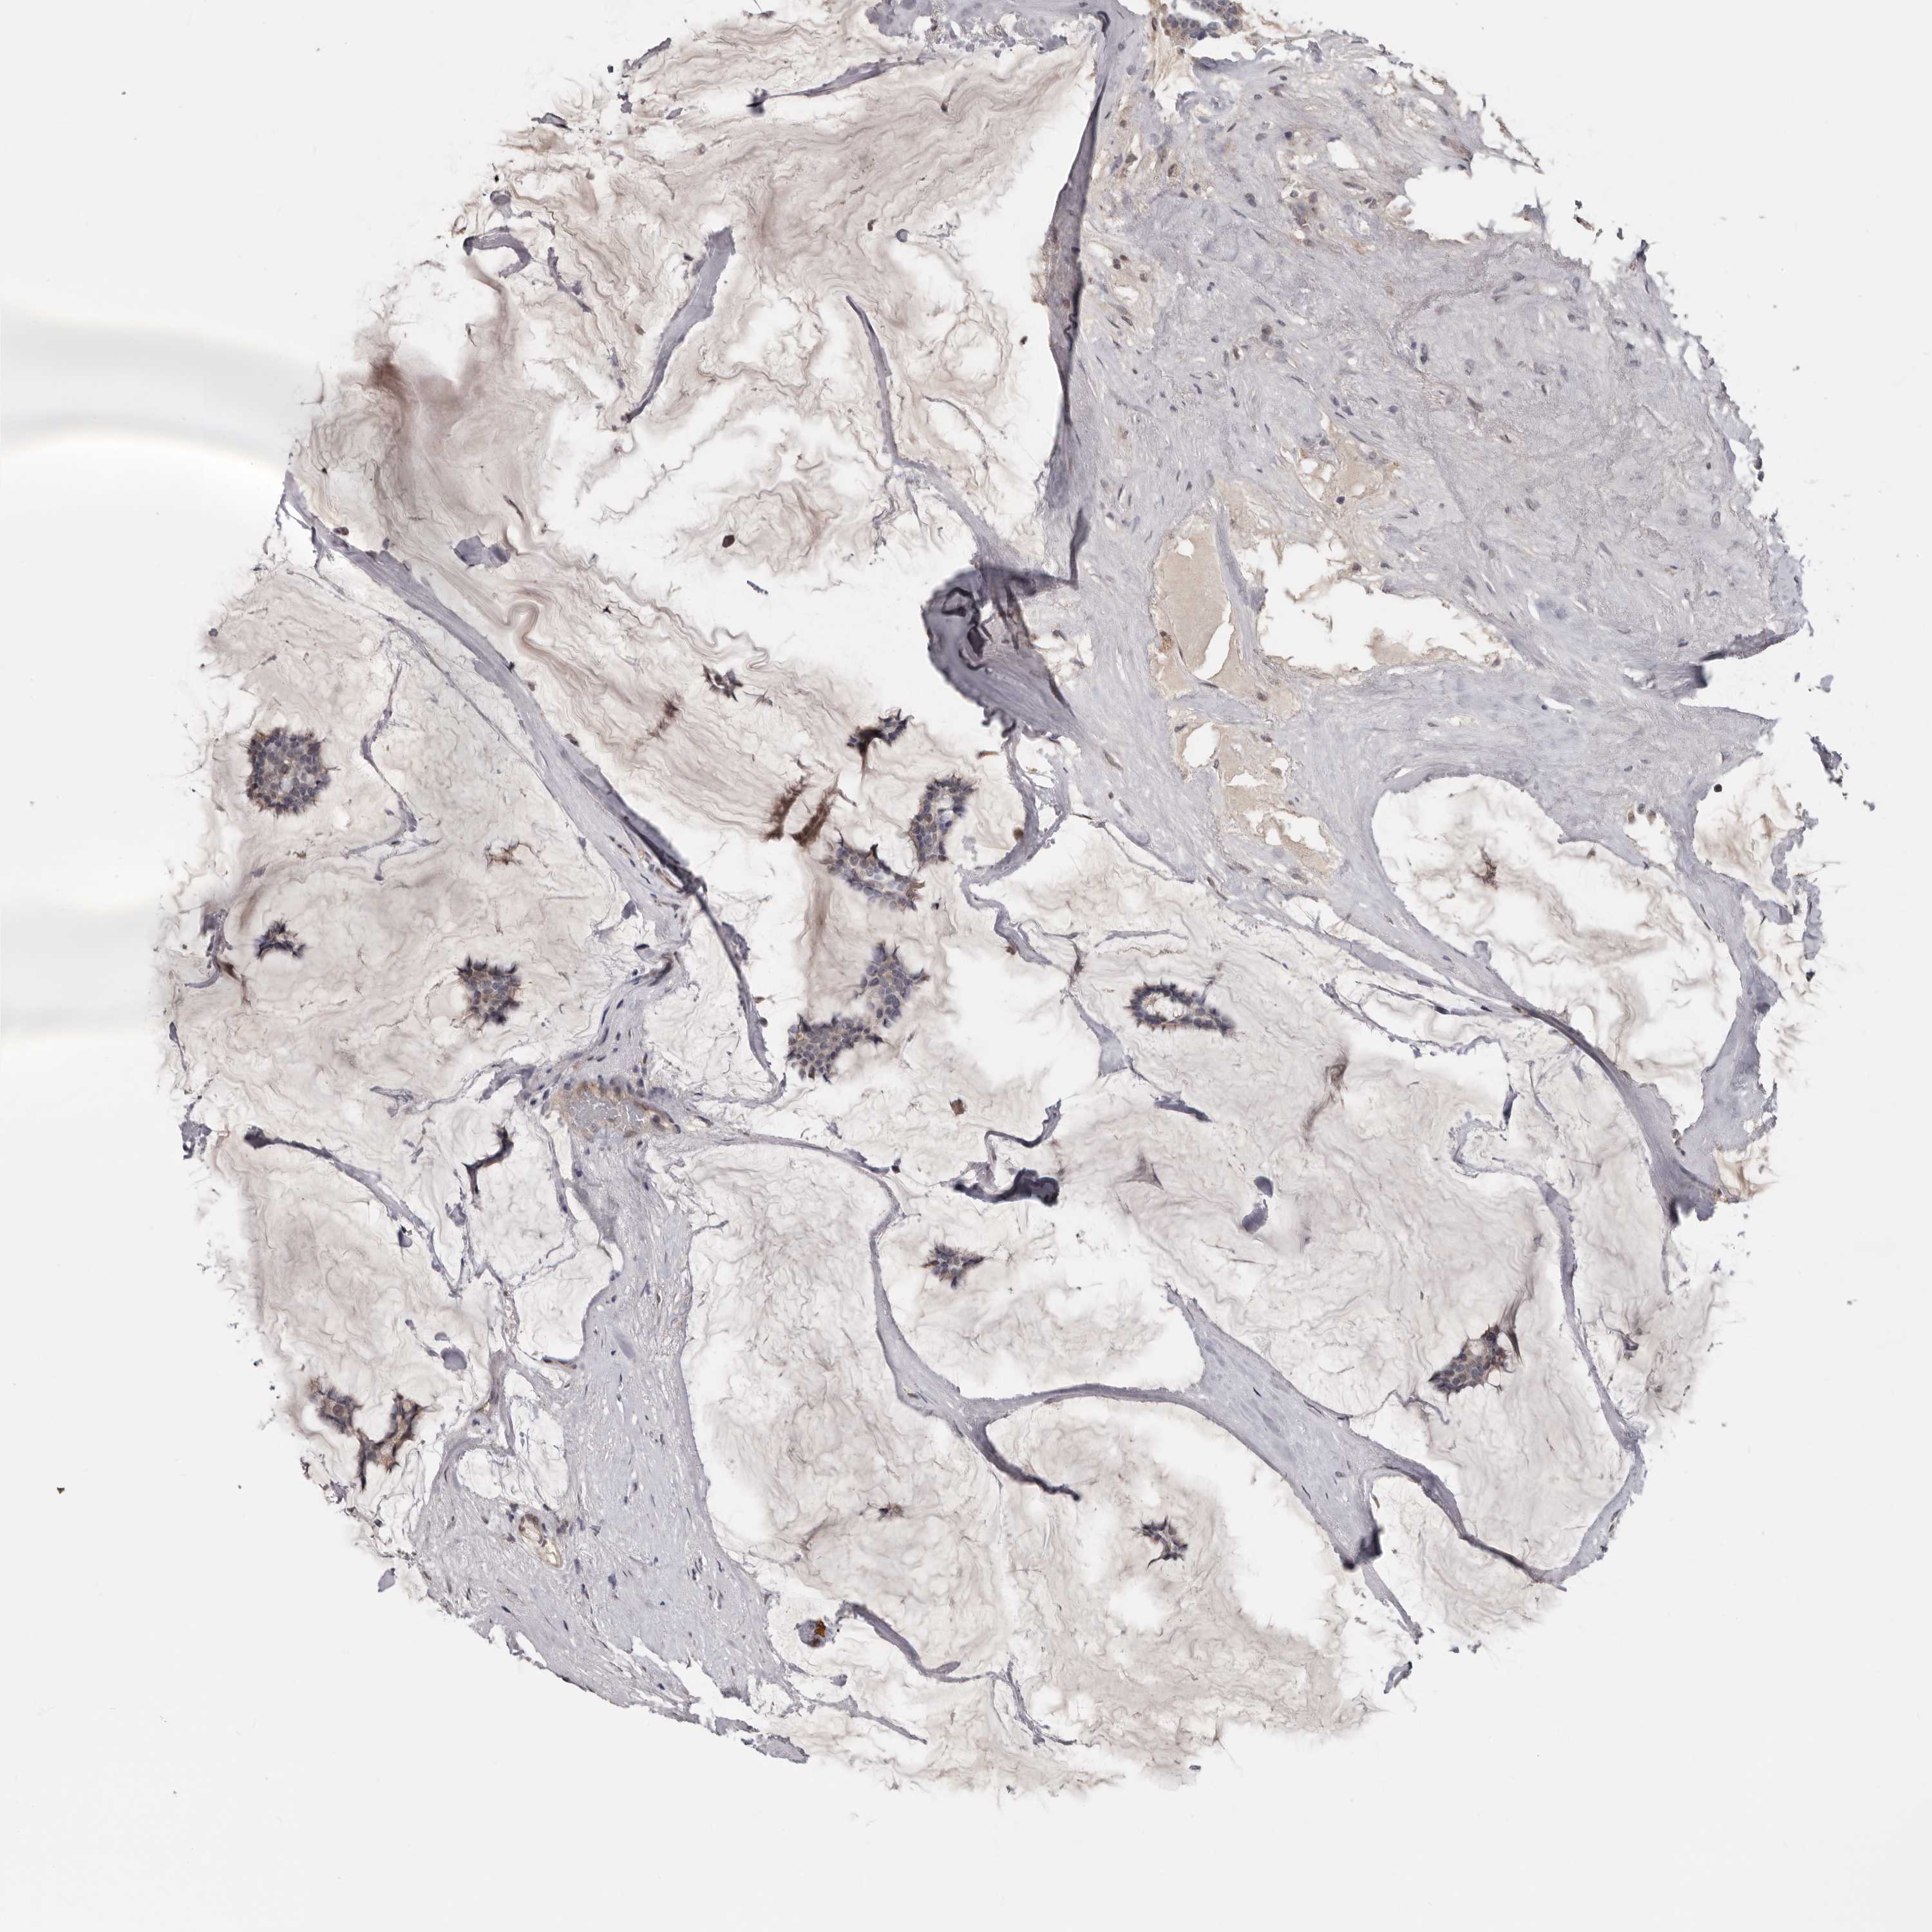

CANCER BREAST CANCER Show tissue menu

BRCA TCGA BRCA VALIDATION PROTEIN EXPRESSION